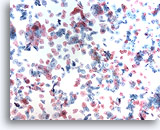

Lubricant A treated vial

…shows the effect of excessive lubricant. Superficial and Intermediate cells are clumped into a three dimensional group. Cells are less evenly dispersed with scant amorphous material noted in the background suggestive of lubricant.

10x

Lubricant A treated vial

…shows the effect of excessive lubricant. Superficial and Intermediate cells are clumped into a three dimensional group. Cells are less evenly dispersed with scant amorphous material noted in the background suggestive of lubricant.

10x